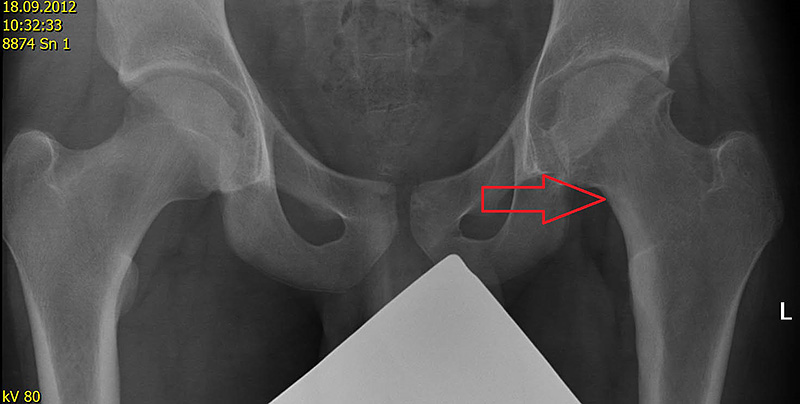

Obr. 2 Osteoidní osteom v CT obraze